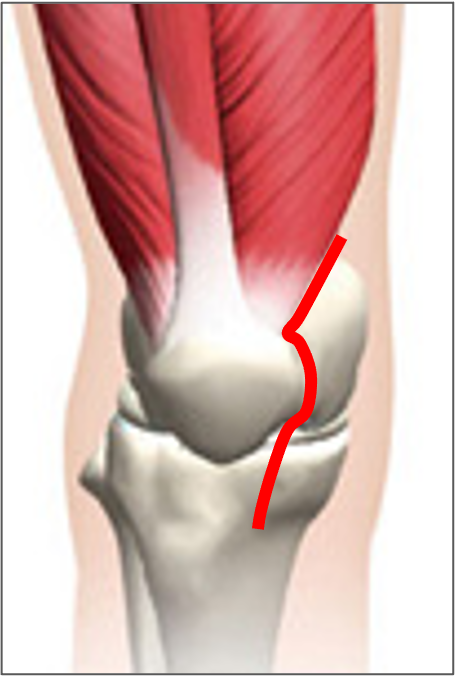

一般的には、内側広筋の一部を切開するMedial parapatellar approachが用いられます。視野がよく手技も簡単であるという利点がありますが、筋肉を大きく切ることで術後の痛みや筋力低下が問題となることがあります。術後の回復を第一に考え、当院ではUnderVastus approach(アンダーバスタスアプローチ)を取り入れ、出来るだけ筋肉を切らない方法でダメージの少ない手術を心がけています。ただし高度な技術が必要であり、変形の程度に応じてアプローチは使い分け、症例に応じて臨機応変に対応しています。

Medial parapatellar approach

内側広筋を大きく切開する

(青:関節包の切開線)

Under Vastus approach

筋肉を温存する

(赤:関節包の切開線)